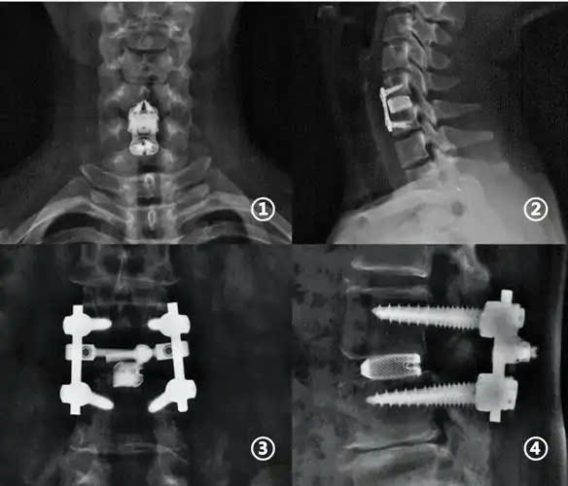

Hình ảnh hạn chế: Hợp kim titan có thể tạo ra các hiện vật kim loại trong quá trình chụp CT hoặc MRI, làm ảnh hưởng đến độ rõ nét của hình ảnh ở các vùng như khớp háng và cột sống, trước khi chụp CT tăng cường, hãy thông báo cho bác sĩ về bất kỳ implant nào bạn đang có.